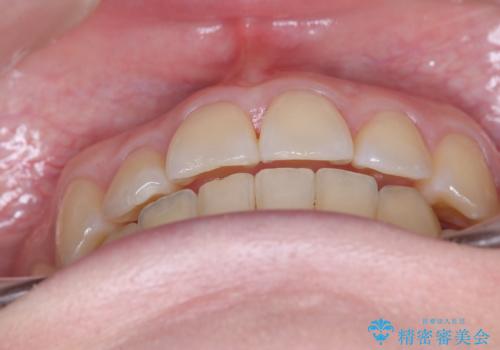

結婚式に向けた歯列矯正

- 患者様は、結婚式までに歯並びを整えたいとのご要望で来院されました。診断の結果、上下左右の第一小臼歯を抜歯し、歯列全体を整える計画としました。審美性を重視し、目立ちにくいホワイトワイヤーを使用した矯正を提案しました。治療期間は2年を目安とし、結婚式までに前歯の整列と噛み合わせを優先的に整えるスケジュールで進めました。定期的な調整と経過観察を通じて、計画的に治療を進めました。

結婚式までに仕上げるため、通常よりも細かく調整を行い、歯の動きを効率的に管理しました。審美ワイヤーを使用したことで、治療中も目立ちにくく、写真撮影などの日常生活での見た目の負担を軽減しました。抜歯部分のスペースを閉じる際には、前歯の位置や噛み合わせのバランスに配慮し、過度な力がかからないよう進めました。患者様の大切なイベントに間に合うよう治療計画を立て、理想的な仕上がりを実現しました。